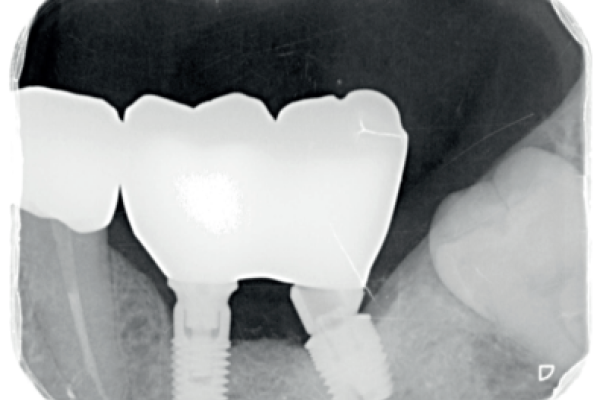

Análisis de los tejidos peri-implantarios en implantes anteriores: relación entre la presencia o ausencia de tabla ósea y el Pink Esthetic Score